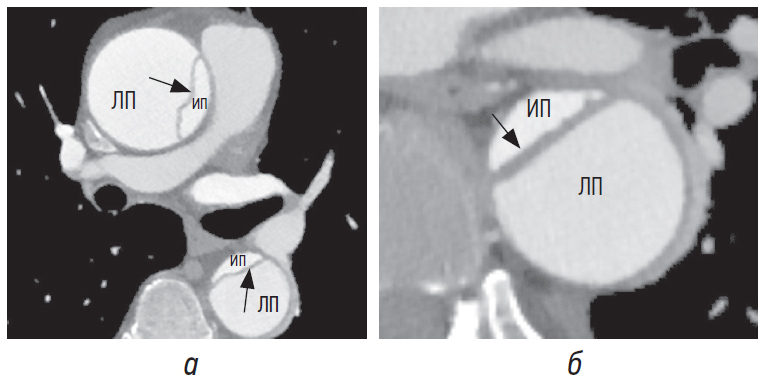

Наиболее часто определяемым признаком, который позволяет надежно отличить ложный просвет от истинного, является так называемый признак «клюва» [4, 5, 8]. Он визуализируется в поперечном сечении аорты и представляет собой острый угол при диссекции аорты. Грани угла формируются наружной стенкой аорты на краю ложного просвета и интимомедиальным лоскутом (рис. 4, а, б).

Рис. 4. Признак «клюва» в восходящем отделе аорты (а), в нисходящем отделе аорты (б) (белые стрелки) без признаков тромбоза. Интимомедиальный лоскут отмечен черными стрелками. ИП — истинный просвет, ЛП — ложный просвет ЛП

Пространство, образованное острым углом, может быть заполнено гиперденсным содержимым (повышение плотности крови вследствие контрастного усиления) (рис. 4, а, б). При заполнении этого пространства гиподенсным содержимым, соответствующим частичному/полному тромбозу, угол притупляется (рис. 5, а, б) [4, 5, 8]. Признак «клюва» наблюдается только в ложном просвете во всех случаях острой и хронической диссекции [8].

Рис. 5. Признак «клюва» при частичном (а) и тотальном тромбозе (б) в нисходящем отделе аорты (белые стрелки). ИП — истинный просвет, ЛП — ложный просвет